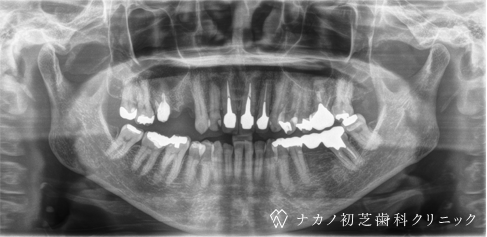

インプラント・2本 (50代女性)

-

BEFORE

AFTER

年齢 50代女性

治療内容 インプラント治療2本(骨造成と歯肉移植の併用)

インプラント治療とは、歯を抜いた所にチタン製の人工歯根を埋入し、その上に歯を入れる方法です。骨と歯肉を増やすことで、より審美的に治療が出来ました。費用 1本 400,000円(税込 440,000円)

リスク・副作用

腫れ・疼痛・違和感を感じるなどの症状を生じることがあります。